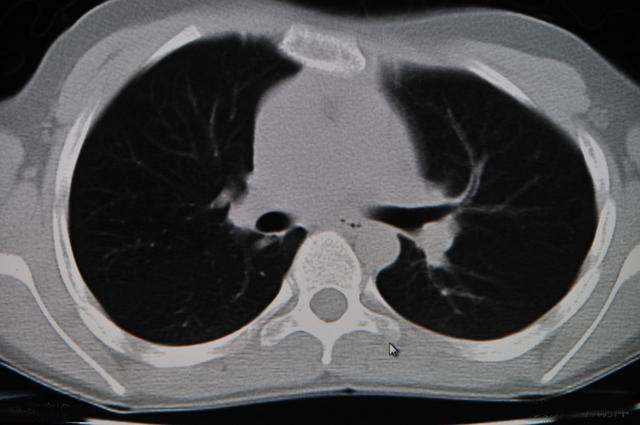

因此,检查类似于肿瘤这样的恶性疾病,不适合仅使用胸片,最好结合胸部CT来看,胸部CT的原理相当于将人体切片并一片一片的观察, 肺部上下前后的病灶都一览无遗,1mm以上的病灶基本上不会遗漏,尤其是1cm以下在胸片上看不出来的病灶在CT上可以明显看出来。

很多人纳闷,胸部CT上发现了肿瘤怎么还不能诊断,这就好比罪犯找到了,犯罪现场找到了为什么还不能定罪一样,有很多没有找到凶器并确认指纹的案件最后都成了冤假错案,我们诊断肿瘤不仅仅追求90%的准确率,往往需要100%确定才能给患者一个交代,肿瘤诊断上的讹错给患者和患者家庭带来的都是灭顶之灾,因此,在胸部CT找到了肿瘤病灶之后做进一步的有创检查成为必须,只有将肿瘤组织中的细胞或者组织块取出来放在显微镜下观察才能最终确诊病情,眼见才能为实。